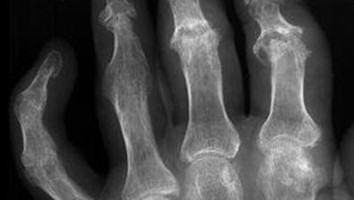

Innovative Strategien für das Management der erosiven Handarthrose

Tabletten werden in Hand geschüttet/© O.Farion / Stock.adobe.com (Symbolbild mit Fotomodell), Mann appliziert Salbe auf sein Knie/© Ake Ngiamsanguan / Getty Images / iStock (Symbolbild mit Fotomodell), Cannabisarzneimittel/© [M] Rocky89 / Getty images / iStock, Störung der Lidhebung bei Myasthenia gravis/© Alessandro Grandini / stock.adobe.com (Symbolbild mit Fotomodell), Arzt untersucht Patient mit Rückenschmerzen/© gilaxia / Getty Images / iStock (Symbolbild mit Fotomodellen), Junger bärtiger Mann liegt im Bett und hält sich die Stirn/© kleberpicui - stock.adobe.com (Symbolbild mit Fotomodell), Vordere Kreuzbandruptur/© Springer-Verlag Berlin Heidelberg 2016, Liposarkom des Funiculus spermaticus/© Springer Medizin Verlag GmbH, Behandschuhte Hände drücken Stumpf nach Amputation/© Vitaly Zubrytsky / stock.adobe.com (Symbolbild mit Fotomodellen), Untersuchung des Beins eines Patienten/© Visionär / Fotolia, Mann erhält einen CT-Scan /© Mark Kostich / stock.adobe.com (Symbolbild mit Fotomodell), Arzt untersucht Senior am Rücken/© miodrag ignjatovic / Getty Images / iStock (Symbolbild mit Fotomodellen), Bildgebung verschiedener interstitieller Lungenerkrankungen/© Christoph Lederer et al. / all rights reserved Springer Medizin Verlag GmbH, Kleinkind und Teddy mit Verband/© simoningate / Getty Images / iStock (Symbolbild mit Fotomodell), Frau unkenntlich fasst sich ans Knie/© Pornpak Khunatorn / Getty Images / iStock (Symbolbild mit Fotomodell), Ein älteres Paar läuft mit Stöcken im Wald/© Roman / Stock.adobe.com (Symbolbild mit Fotomodell), Illustration zur künstlichen Intelligenz/© Toowongsa / Stock.adobe.com (Symbolbild mit Fotomodell), Ärztin untersucht Patientin mit Knieschmerz/© Jirapong / Stock.adobe.com (Symbolbild mit Fotomodell), Arzt untersucht älteren Mann/© contrastwerkstatt / Stock.adobe.com (Symbolbild mit Fotomodellen), Blutabnahme/© Yakobchuk Olena / stock.adobe.com (Symbolbild mit Fotomodell), Point-of-care-Ultraschall bei Trauma/© Vicent O et al. / all rights reserved Springer Medizin Verlag GmbH, Röntgenbild Kiefer/© Aniuszka / Fotolia (Symbolbild mit Fotomodell), Box mit Tabletten/© ekachai050050 / stock.adobe.com (Symbolbild), Manuelle Behandlung unterer Rückenschmerzen/© Viorika / Getty Images / iStock (Symbolbild mit Fotomodellen), Operationssaal-Korridor /© h368k742 / stock.adobe.com, Ohnmächtige ältere Frau/© Satjawat / stock.adobe.com (Symbolbild mit Fotomodellen), Akupunktur/© (M) geargodz / stock.adobe.com (Symbolbild mit Fotomodell), Hand greift nach Skalpell/© Morsa Images / Getty Images / iStock, Gruppe beim Rückentraining im Fitnesscenter/© Robert Kneschke / stock.adobe.com (Symbolbild mit Fotomodellen), Mann auf dem Bau/© pololia / Stock.adobe.com (Symbolbild mit Fotomodell), Psychotherapeutische Sitzung/© PeopleImages / Getty Images / iStock (Symbolbild mit Fotomodellen), Frau sitzt besorgt beim Arzt und hält sich den Kopf/© M+Isolation+Photo / Stock.adobe.com (Symbolbild mit Fotomodell), Seniorin liegt reglos auf Boden/© Racle Fotodesign / stock.adobe.com (Symbolbild mit Fotomodell), Medizinisches Personal hält verschiedenfarbige Kinesiotapes/© Татьяна Волкова / stock.adobe.com (Symbolbild mit Fotomodell), Ärztin in Op.-Kleidung/© shapecharge / Getty Images / iStock (Symbolbild mit Fotomodell), Skoliose/© Springer Medizin, Vordere Kreuzbandruptur/© Müller P E & Niethammer T R / all rights reserved Springer Medizin Verlag GmbH, Rettungsdienst/© huettenhoelscher / Getty images / iStock (Symbolbild mit Fotomodellen), Person hält zwei Tabletten in der Hand/© AsiaVision / Getty Images / iStock (Symbolbild mit Fotomodell), Video-Therapie /© Valerii Honcharuk / stock.adobe.com (Symbolbild mit Fotomodellen), Ältere Person hält sich das Knie/© ZayNyi / Stock.adobe.com (Symbolbild mit Fotomodell), Fallbeispiel Röntgenaufnahme des Thorax in zwei Ebenen/© Reinke L. et al. / all rights reserved Springer Medizin Verlag GmbH, Kleiner Junge nach Fahrradunfall/© JohnAlexandr / Getty Images / iStock (Symbolbild mit Fotomodell), Läufer umfasst sein Sprunggelenk/© PeopleImages / Getty Images / iStock (Symbolbild mit Fotomodell), Mann mit Knieschmerzen/© Rockaa / Getty Images / iStock (Symbolbild mit Fotomodell), Vorbereitung eines periphere Venenverweilkatheter/© Seppographie / stock.adobe.com, Springer Medizin Podcast - Stürze im Alter/© Gatz M et al / all rights reserved Springer Medizin Verlag, Orthese und Gehhilfen/© Ralf Geithe / stock.adobe.com (Symbolbild mit Fotomodell), Mann geht mit Hund an der Leine spazieren/© K. Thalhofer / stock.adobe.com (Symbolbild mit Fotomodell), Schenkelhalsfraktur prä- und postoperativ/© Henze K et al. / all rights reserved Springer Medizin Verlag GmbH, Älterer Arzt mit Arzthelfer schauen über Patientenakte/© stokkete / stock.adobe.com (Symbolbild mit Fotomodellen), Röntgenbild Hand/© Mathias Weil / stock.adobe.com, Hinweisschild Notaufnahme/© huettenhoelscher / Getty images / iStock, Frau sitzt vor mehreren Bildschirmen/© Baba Images / stock.adobe.com (Symbolbild mit Fotomodell), Junge Ärztinnen und Ärzte diskutieren/© fizkes / stock.adobe.com (Symbolbild mit Fotomodellen), Systemischer Lupus erythematodes Gesicht Mann/© velimir / Stock.adobe.com (Symbolbild mit Fotomodell), Operation Karpaltunnelsyndrom/© Gardinovacki / Getty Images / iStock (Symbolbild mit Fotomodell), CAR-T-Zellen/© Meletios Verras / Getty Images / iStock, Ärztin untersucht älteren Mann/© Drazen Zigic / Getty Images / iStock (Symbolbild mit Fotomodellen), Frau zieht Patientin Thrombosestrumpf an/© tibanna79 / stock.adobe.com (Symbolbild mit Fotomodellen), Wirbelsäulen-MRT bei Patient mit axialer Spondyloarthritis/© Springer Medizin, Frau bei Knochenmineraldichte-Messung/© gelmold / stock.adobe.com (Symbolbild mit Fotomodell), Psoriasisarthritis /© Springer Medizin, Anatomischer Überblick Handgelenk/© Deglmann CJ / all rights reserved Springer Medizin Verlag GmbH, Frau mit Hut im Wald/© (M) encierro / stock.adobe.com (Symbolbild mit Fotomodell), Rheumatoide Arthritis in den Händen/© RFBSIP / stock.adobe.com (Symbolbild mit Fotomodell), Frau und Mann joggen im Wald/© Harbucks / Getty Images / iStock (Symbolbild mit Fotomodellen), Frau mit Knieschmerzen/© shurkin_son / Getty Images / iStock (Symbolbild mit Fotomodell), Hallux valgus/© masanyanka / stock.adobe.com, Raucher Zigarette Rauch /© buenaventura13 / stock.adobe.com (Symbolbild mit Fotomodell), Magnetresonanztomographie/© Svitlana / Stock.adobe.com (Symbolbild mit Fotomodell), Anästhesistin im OP/© stefanamer / Getty Images / iStock (Symbolbild mit Fotomodellen), Verband an Unterschenkelstumpf wird angelegt/© angkhan / stock.adobe.com (Symbolbild mit Fotomodellen), Schreiendes Baby/© AzmanL / Getty Images / iStock (Symbolbild mit Fotomodell), Narbe nach Kniegelenkersatz/© Miriam Dörr / Fotolia (Symbolbild mit Fotomodell), Mann untersucht Frau an der Lende/© pololia / stock.adobe.com (Symbolbild mit Fotomodell), Gebrochener Arm eines Kindes erhält Gips/© Rafael Ben-Ari / stock.adobe.com (Symbolbild mit Fotomodellen), Unikompartimentelle Knieprothese/© NICOLAS LARENTO / stock.adobe.com, Frankfurt am Main an einem heißen Sommertag mit strahlender Sonne und großem Thermometer/© Günter Albers / Stock.adobe.com, Infantiles Hämangiom/© tolgart / Getty Images / iStock (Symbolbild mit Fotomodell), Zecke auf menschlicher Haut/© sasel77 / stock.adobe.com, Urinbecher und Urinanalyse-Streifen/© RHJ / Stock.adobe.com, Walking mit Kniebandage/© Suzi Media Production / Getty Images / iStock (Symbolbild mit Fotomodell), Fraktur der lateralen Condyle des Humerus im Röntgenbild/© Susmit / stock.adobe.com, Arzt untersucht Knie einer Seniorin/© FluxFactory / Getty Images / iStock (Symbolbild mit Fotomodellen), Röntgenbild einer Psoriasis-Arthritis/© Springer Medizin Verlag GmbH, Frau macht Gymnastikübung in ihrem Schlafzimmer/© Krakenimages.com / stock.adobe.com (Symbolbild mit Fotomodell), Abklärung von Rückenschmerz bei älterer Patientin/© andreswd / Getty Images / iStock (Symbolbild mit Fotomodellen), Physiotherapeut behandelt Patientin an Schulter/© © contrastwerkstatt / stock.adobe.com (Symbolbild mit Fotomodellen), Wald/© alexugalek / stock.adobe.com, Arthropedia, Kinesiotape um das Knie herum/© baranq / stock.adobe.com (Symbolbild mit Fotomodell), Röntgenbild eines künstlichen Hüftgelenks/© Nicolas Larento / Fotolia, Prähabilitation am Fußgelenk/© herraez / Getty Images / iStock (Symbolbild mit Fotomodellen), Junge Ärztin vor einem Triage-Zelt/© Milos / Stock.adobe.com (Symbolbild mit Fotomodell)